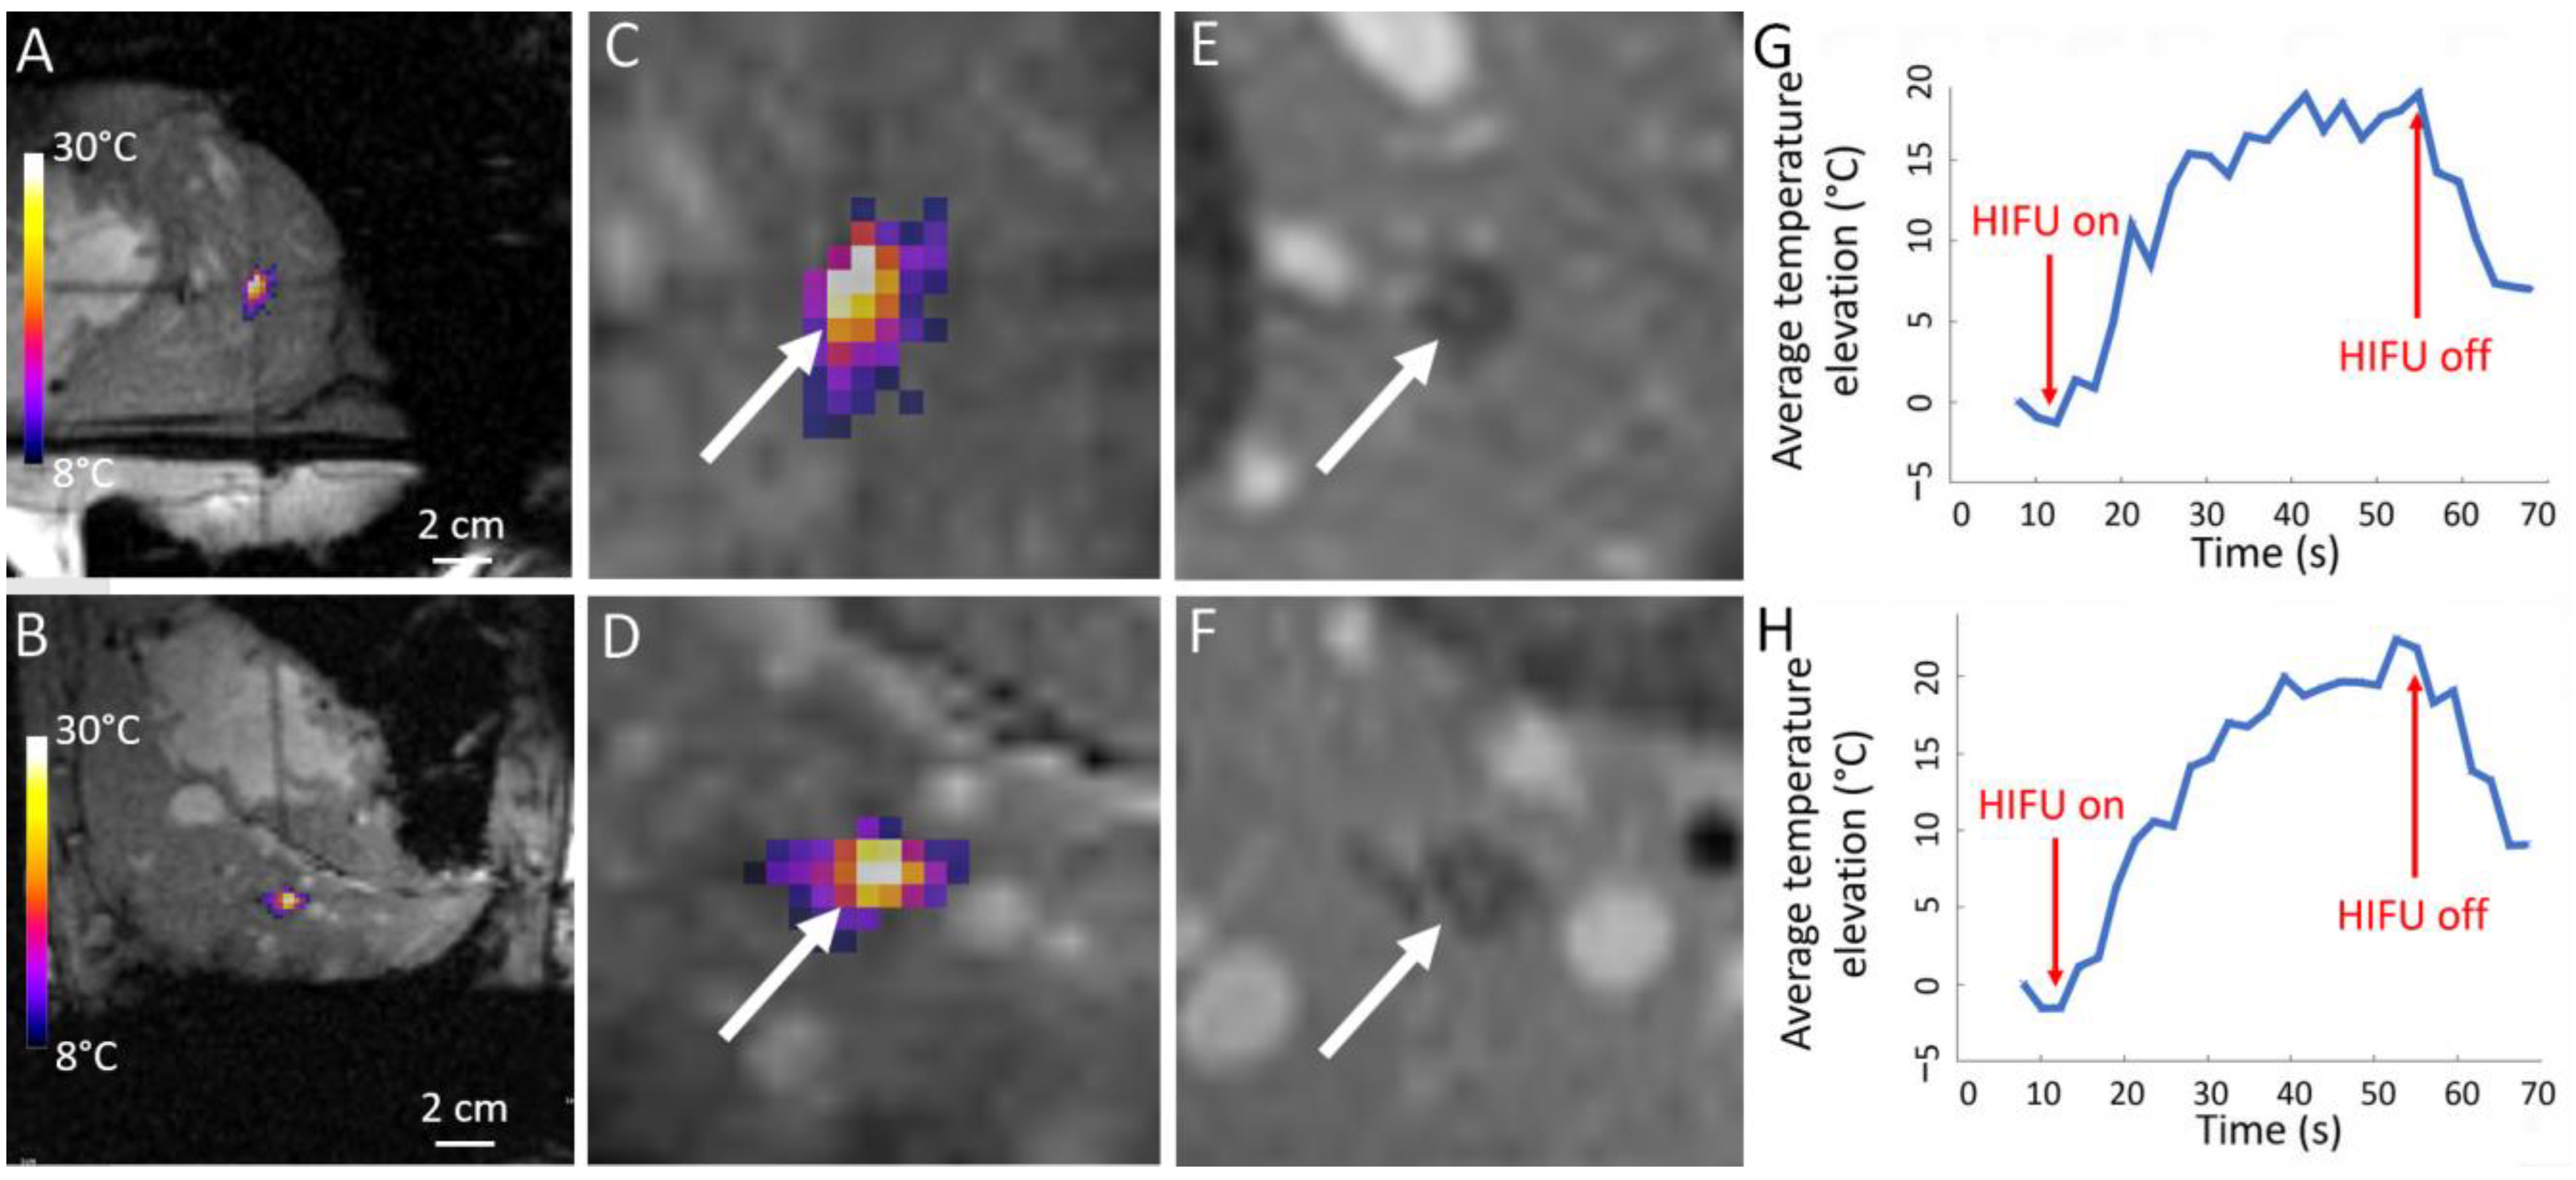

| Pig | RF Ablation Size (mm3), from MR Images (along AP, LR and HF Axes) | Temperature Reached During HIFU Ablation (°C) | HIFU Ablation Longest Axis (mm) from MR Images; See Figure 6 and Figure 7 | HIFU Ablation Longest Axis (mm), from Gross Pathology; See Figure 6 and Figure 7 | Planned Center-to-Center Distance between the RF and MRgHIFU Ablations (mm), from MR Images | Center-to-Center Distance between the RF and MRgHIFU Ablations (mm), from Gross Pathology | Center-to-Center Distance between the RF and MRgHIFU Ablations (mm), from MR Images | Near-Field Side Effects Grade |

|---|---|---|---|---|---|---|---|---|

| 1 | 4.9 × 6.1 × 4.8 | 63 | - | - | 0 | - | - | 1a |

| 2 | 7.2 × 6.3 × 9.2 | 86 | 6.9 | - | 11.8 | - | 10.1 | 1a |

| 3 | 4.6 × 3.7 × 4.5 | 85 | 15.8 | 16.5 | 6.7 | 3.6 | 3.2 | 1a |

| 4 | 6.7 × 6.1 × 6.8 | 86 | 7.4 | 7.9 | 16.1 | 16.0 | 16.2 | 1a |

| 5 | 5.1 × 4.7 × 6.2 | 62 | 21.1 | 23.2 | 18.4 | 24.2 | 24.1 | 1a |

| 6 | 3.0 × 4.6 × 5.5 | 58 | 14.0 | 15.0 | 11.2 | 10.3 | 10.3 | 1b |